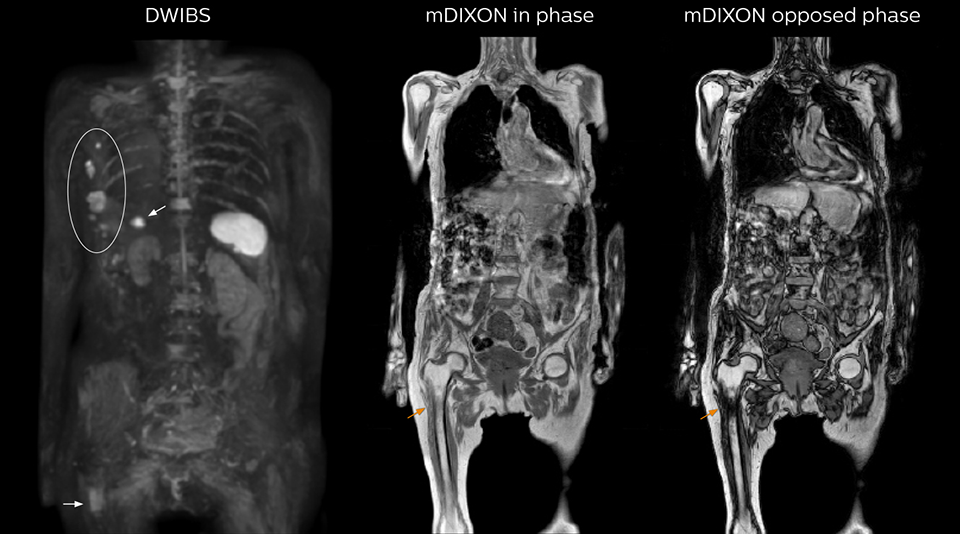

mDIXON FFE enriches the whole body exam without scan time penalty

Kawasaki Sawai Hospital’s whole body protocol also includes an mDIXON FFE sequence. Because mDIXON provides images for four contrast types – water only, fat only, in-phase and out-of-phase – from a single acquisition, it is useful in many ways.

“mDIXON FFE allows us to quickly get information we need to assess the presence of fat. That gives us more information when we need to diagnose bone lesions, and when we are asked to judge fat-containing lesions such as hepatocellular or renal carcinoma,” Dr. Nobusawa says.

“The mDIXON fat images can help us to differentiate fatty bone marrow from bone lesions. This is especially useful in elderly people, who tend to have fattier bone marrow. The water images provide a high signal-to-noise ratio in the intestinal canal, which is valuable for visualizing lesions in the colon,” he says.

“In-phase and out-phase sagittal T1-weighted FFE images help us to visualize and further characterize bone lesions such as metastasis and bone-marrow hyperplasia that have high signal on DWI. These images are also used throughout radiotherapy, to monitor changes in the fatty bone marrow.”